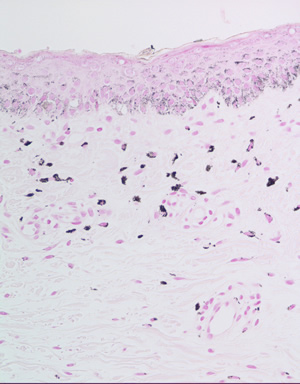

×200